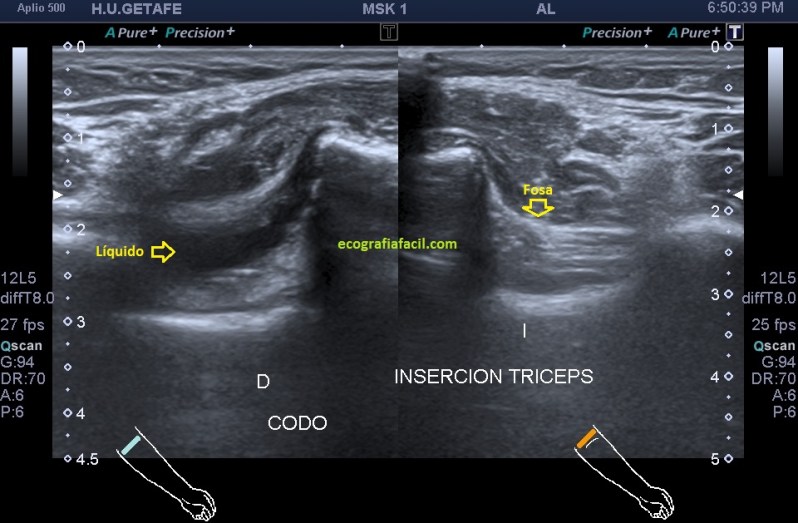

Una de las imágenes más importantes del protocolo de codo es el corte longitudinal de la región posterior para el estudio de la inserción del tríceps en olécranon, pero no solo por esta inserción, me explico…una de las regiones que exploramos en este corte es la fosa olecraniana, que como puedes ver en la imagen es medial y profunda, hiperecogénica en situación normal y donde la presencia de líquido es signo inequívoco de patología locoregional. Además es uno de los objetivos que buscamos en este estudio y por eso siempre documentamos con esta imagen.

En la imagen 5 puedes ver este signo que te cuento, en el codo afectado y te pongo la imagen comparativa del lado contralateral para que veas cómo es normalidad y cómo es patología. Te marco la anatomía ecográfica, es una imagen muy bonita y fácil de ver, si vas a ver inserción aplica la técnica apropiada que te recomendé en el protocolo de codo en este post.

5